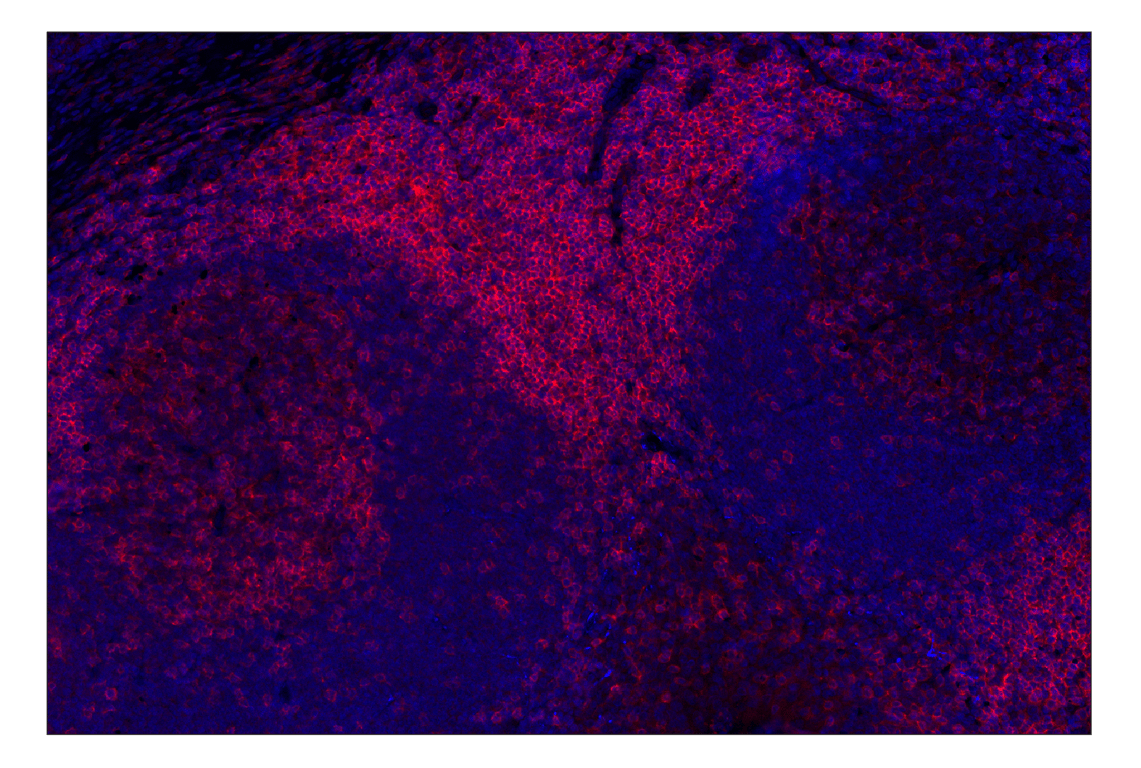

CD4 (MSVA-004R) Rabbit Monoclonal Antibody (Alexa Fluor® 647 Conjugate) #40568

This Cell Signaling Technology® antibody is conjugated to Alexa Fluor® 647 fluorescent dye under optimal conditions. This antibody conjugate is expected to exhibit the same species cross-reactivity as the unconjugated CD4 (MSVA-004R) Rabbit mAb #99785.

Immunohistochemistry (Paraffin) 1:50

CD4 (MSVA-004R) Rabbit Monoclonal Antibody (Alexa Fluor® 647 Conjugate) recognizes endogenous levels of CD4 protein.

Human

Cluster of Differentiation 4 (CD4) is a glycoprotein composed of an amino-terminal extracellular domain (four domains: D1-D4 with Ig-like structures), a transmembrane part, and a short cytoplasmic tail. CD4 is expressed on the surface of T helper cells, regulatory T cells, monocytes, macrophages, and dendritic cells, and plays an important role in the development and activation of T cells. On T cells, CD4 is the co-receptor for the T cell receptor (TCR), and these two distinct structures recognize the Antigen–Major Histocompatibility Complex (MHC). Specifically, the D1 domain of CD4 interacts with the β2-domain of the MHC class II molecule. CD4 ensures specificity of the TCR–antigen interaction, prolongs the contact between the T cell and the antigen presenting cell, and recruits the tyrosine kinase Lck, which is essential for T cell activation (1).